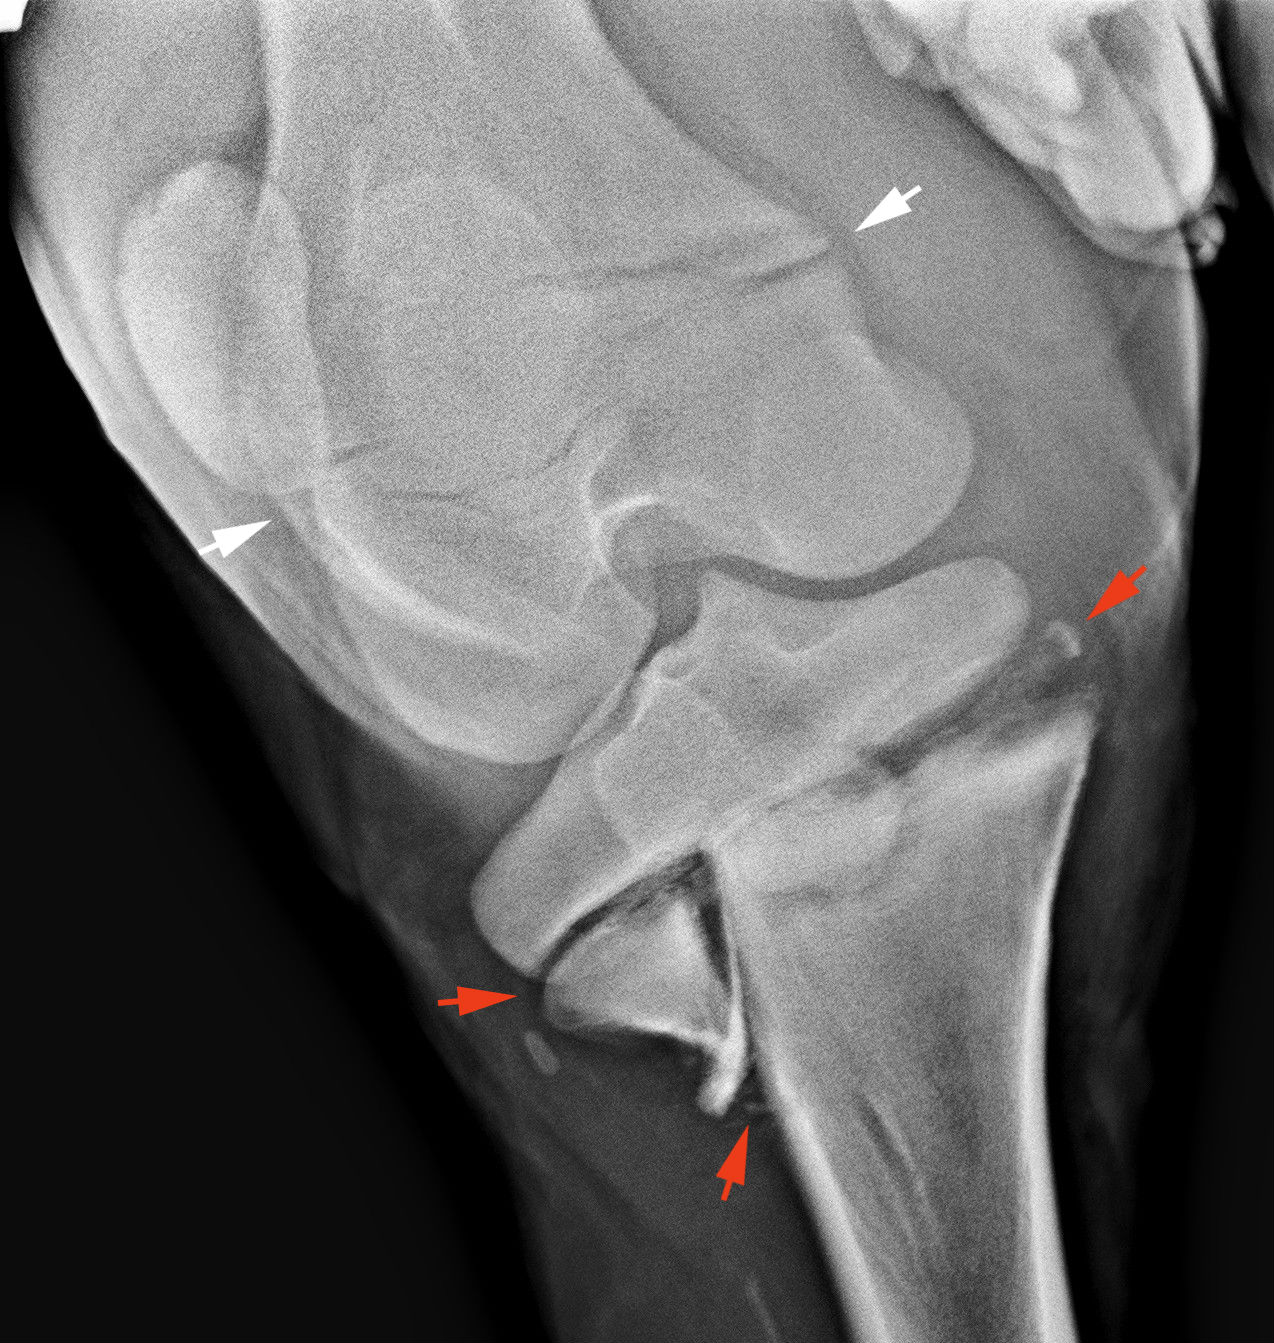

Fiatal csikó sípcsont törése. A piros nyilak a törést mutatják. A fehér nyilak az un. növekedési zóna vékonyabb vonalát mutatják - ez a csont növekedésének színhelye. Ez a csikó meggyógyult konzervatív kezelés mellett.